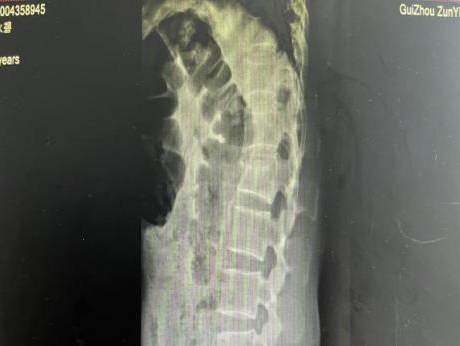

为提升区域内基层医疗机构糖尿病足诊疗服务能力、促进青年医师对糖尿病足的规范化诊治水平,遵义市第二城市医疗集团总院(贵州航天医院)圆满举办贵州省继续医学教育项目——胫骨横向骨搬移技术治疗糖尿病足专题研讨班。 贵州航天医院党委委员、副院长彭亮出席会议并致辞,遵义市第二城市医疗集团各成员单位,以及红花岗区、汇川区、绥阳县、桐梓县等多个区县的基层医疗机构骨干医师参加会议。 研讨班 本次研讨班以胫骨横向骨搬移技术在糖尿病足治疗中的应用为核心主题,围绕糖尿病药物治疗与生活方式管理策略、围手术期血糖精准调控要点、胫骨横向骨搬移技术典型病例深度解析、糖尿病足的临床分型与个体化治疗方案制定等临床实践中的热点与难点展开深入探讨,通过专题授课、案例研讨、互动交流等多元化形式,为参会者搭建了理论与实践结合的学习平台。 此次研讨班不仅为区域内基层医院搭建了学术交流与经验共享的平台,更对推动糖尿病足预防、诊断与治疗的规范化、系统化发展起到了积极作用,有效助力青年医师更新专业知识体系、提升临床技能,为进一步保障区域内糖尿病足患者的健康奠定了坚实基础。 贵州航天医院骨科专家简介 陈明勇 骨一科主任,副主任医师 临床擅长:从事创伤骨科工作约20年,对骨缺损、骨不连、骨肿瘤、肢体畸形等的肢体矫形重建及功能重建,慢性化脓性骨髓炎的根治治疗、糖尿病足的保肢治疗、快速康复理念(ERAS)下的老年骨折的诊治,四肢复杂骨折的诊治,四肢骨折等微创手术治疗具有丰富的临床经验。 2004年毕业于遵义医学院临床专业,曾在中国人民解放军总医院、广西医科大学第一附属医院、上海第六人民医院骨科进修。中国中西医结合学会骨伤科专业委员会横向骨搬移治疗糖尿病足及微血管网再生学组首届委员,遵义市医学会创伤分会常务委员。 瞿 晖 骨科党支部书记,骨二科主任,副主任医师 临床擅长:对骨科的常见病、关节外科、脊柱外科及运动医学疾病的诊治具有丰富的临床经验,熟练掌握骨科手术操作技术。 毕业于遵义医学院临床医学系,2005年前往广州中山大学第一附院骨显微医学部进修学习,2011年前往成都华西医院进修学习,并多次在省内外学习骨科相关知识,是中华医学会骨科分会会员。 赵小锋 中共党员,骨二科副主任,副主任医师 临床擅长:从事骨科临床工作11年,对骨科常见病、多发病诊疗有较为丰富的临床经验,擅长脊柱相关疾病诊断及治疗,尤其是颈、腰、腿疼痛疾病诊断及治疗,擅长胸腰椎骨折微创经皮穿刺内固定术、经皮穿刺椎体成形术、经皮穿刺脊柱内镜下腰椎间盘摘除术、单纯开创腰椎间盘摘除术、腰椎滑脱复位椎间植骨椎融合内固定术、腰椎管狭窄减压融合内固定术及人工髋、膝关节置换术等。 2012年毕业于遵义医学院外科学专业硕士研究生,2019年参加“遵义市115医学人才精英计划”于上海交通大学第一附属医院培训学习,2023年于北京大学第三人民医院脊柱外科进修学习,曾获得遵义市优秀医师荣誉称号。 遵义市手外科第一届委员,遵义市医学会创伤分会第一届委员,遵义市医学会创伤分会第二届委员,贵州省康复医学会第三届脊柱脊髓专业会委员,遵义市医学会烧伤与整形外科学分会委员,发表论文5篇,其中国家级核心期刊1篇,SCI论文1篇,主持市级课题1项并结题,参与市级课题2项。 赵兴东 骨科主任医师 临床擅长:擅长骨科的常见病及各种创伤、四肢骨折创伤修复、骨感染、手足疾病的诊治和手足体表畸形的矫形整复,熟练掌握骨科四肢骨病及创伤的手术操作技术,尤其在四肢关节复杂性损伤、手足外伤、组织缺损创面、难治创面的皮瓣修复方面及平足、高弓足矫形方面及四肢慢性疼痛诊治、康复方面具有丰富的临床经验。 硕士研究生,毕业于遵义医学院临床外科系,2015年前往山东省立医院手足外科进修学习;遵义市医学分会创伤分会第一、二届委员,遵义市手外科医学会第二委届员会常务委员;在省级及省级以上期刊发表文章9篇,参编著作2部,参与主持并完成市级课题1项,参与市级课题2项、省级课题1项。 张艳金 中共党员,骨科副主任医师 临床擅长:从事骨外科工作16年,对复合伤、多发伤的救治、四肢骨干骨折、关节周围骨折、骨肿瘤、骨髓炎等诊治具有丰富的临床经验。 中共党员,硕士研究生,2006年本科毕业于山西医科大学第二临床医学院,2011年研究生毕业于北京军区总医院;在“老年COPD患者合并髋部骨折的诊治”国际合作课题组研究两年,在老年髋部骨折的诊治方面具有丰富的经验,并发表论文6篇;主持遵义市级课题1项,承担遵义医科大学的临床教学工作,获得遵义医科大学优秀带教老师荣誉。编撰有《骨科疾病诊疗精粹》一书,开展2项新技术,编撰地方规范《务川自治县创伤骨科常见疾病诊疗规范》一书。 张俊凯 骨科副主任医师 临床擅长:从事骨科临床工作28年,对创伤骨折、骨感染、骨缺损、骨不连等外科诊治,四肢骨折的微创手术治疗,四肢复杂骨折(如关节内粉碎性骨折、多发骨折等)的损伤控制及手术治疗等具有丰富的临床经验。 1995年毕业于遵义医学院临床专业,2009年前往复旦大学附属医院骨科进修1年。 卢懿明 中共党员,骨科副主任医师 临床擅长:从事骨科工作18年,对创伤骨折、四肢骨折的微创手术治疗、四肢复杂骨折(如关节内粉碎性骨折、多发骨折等)的损伤控制及手术治疗,尤其是髋部骨折的PFNA等微创技术,踝关节骨折、膝关节周围骨折的Mipo微创技术等具有丰富的临床经验,开展了4项新技术,发明6项新型专利技术。 2005年毕业于遵义医学院临床专业,2017年,前往南方医科大学第三附属医院骨科进修半年,回院后运用Mipo技术对骨干骨折及干骺端骨折的治疗技术,同时积极开展骨盆骨折、髋臼骨折腹直肌外侧切口的应用;发表了多篇专业论文,经常参与省内外学术交流会授课,获得医院荣誉称号多个。 邬夏荣 骨科副主任医师 临床擅长:从事骨科工作16年,对四肢复杂骨折、骨肿瘤的诊治,尤其是足踝创伤、慢性踝关节损伤、平足症等诊疗具有丰富的临床经验。 2006年毕业于遵义医科大学临床医学专业,曾在陆军军医大学西南医院进修学习,发表多篇骨科学术论文。 余德怀 中共党员,骨科副主任医师 临床擅长:从事骨科工作10余年,对运动医学、骨关节、脊柱外科常见病、多发病的诊治具有丰富的临床经验。 硕士研究生,2011年毕业于遵义医学院临床医学专业,曾前往遵义医科大学附属医院运动医学专业进修学习;是贵州省医学会运动医学分会青年委员,西部关节镜联盟委员;发表多篇骨科学术论文。 冯 乾 骨科副主任医师 临床擅长:从事骨科工作近20年,熟练掌握骨科多发病及常见病的诊治,尤其对脊柱退变性疾病的诊断及治疗具有丰富的临床经验,主要研究脊柱微创相关治疗方式,能熟练开展椎间孔镜及UBE。 曾前往北京大学第三医院进修学习疼痛及椎间孔镜、首都医科大学友谊医院专业进修脊柱内镜;是贵州省康复医学会第三届脊柱脊髓专业委员会委员;发明专利3项、发表脊柱外科专业论文多篇。 贵州航天医院骨科简介 基本情况 贵州航天医院(原3417医院)骨科组建于1968年,前身是以创伤和断肢(断指)再植闻名于世的上海市第六人民医院骨科,中国断肢(断指)再植的奠基者、中科院院士陈仲伟等专家莅临科室指导医疗和教学,并在70年代开展了贵州省首例断肢(断指)再植手术。组建50余年来,诊治患者已逾百万,挽救了无数的伤病员,成为了保障遵义地区人民群众健康的重要支撑。 经过几代人的不懈努力,今天的骨科,已由创伤骨科发展至骨病、骨肿瘤、骨结核等领域,现有脊柱外科、关节外科、四肢创伤、手足外科四个亚专科,成为了集医疗、教学、科研于一体的综合学科,是贵州省临床重点专科、遵义市临床重点专科、遵义市骨科临床医学中心、遵义市基层骨科专科联盟理事长单位。 科室目前开放床位110张,共有医护人员50余人,副高级以上专家18人,硕士研究生15人。拥有一流骨科医疗设备多台,每年不定期选派优秀技术骨干到全国各大知名医学院校进修、学习、参观、交流,并邀请国内、国外知名专家教授来院进行交流、指导,通过不断引进国内外先进的诊疗技术,科室医疗技术水平稳步提升,为广大人民群众提供了优质的医疗服务。 专科特色 骨一科 (一)骨缺损、骨不连的肢体与功能重建 胫骨横向骨搬移技术治疗糖尿病足: (二)慢性骨髓炎的根治治疗 (三)肢体缺血性疾病如糖尿病足、脉管炎的保肢治疗 (四)皮瓣修复 (五)复杂创伤的治疗 (六)老年髋部骨折及小儿骨折快速手术 老年髋部骨折: 骨二科 (一)胸腰椎骨折微创经皮椎弓根螺钉固定术 (二)老年性骨质疏松性患者腰椎滑脱脊柱内固定术(骨水泥螺钉) (三)V形双通道脊柱内镜技术(VBE)腰椎融合术治疗腰椎退行性疾病 (四)老年性骨质疏松性骨折(PVP/PKP)术 (五)人工髋关节置换术 (六)双侧股骨头坏死人工全髋关节置换 (七)右侧全髋置换术后假体周围骨折翻修 (八)人工膝关节置换术 (九)人工膝关节假体松动翻修 (十)关节镜技术 传统手术切口 关节镜技术切口 诊疗范围 骨一科 1.四肢创伤、矫形。 2.手、足踝外科。 骨二科 End